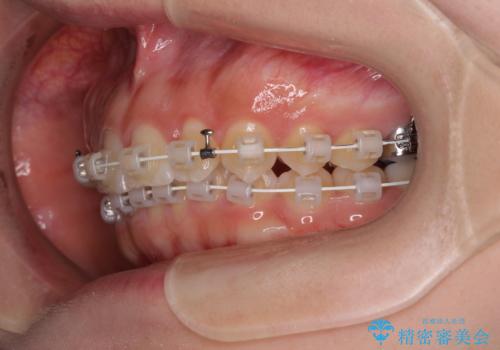

- 審美装置

- 1年3ヶ月

短期間で確実に仕上げたいとのことで、アンカースクリューと補助装置を併用して歯列の後方移動を図り、ワイヤー装置にて矯正治療を行うこととしました。

左上の歯列は補助装置により速やかに移動し、1年程度で奥歯の咬み合わせが改善され、1年3ヶ月の短期間でしっかりと仕上げることができました。